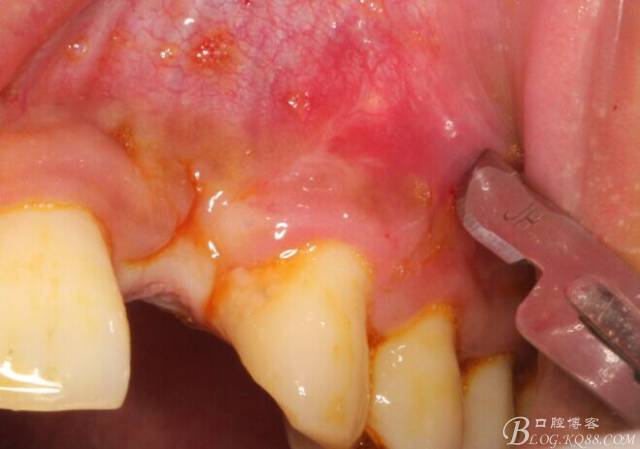

于是我果斷告知患者,手術(shù)失敗了,不能拖延,如不及時(shí)處理,炎癥繼續(xù)發(fā)展會(huì)很快波及鄰牙牙槽骨?;颊呓邮芪业慕ㄗh。切開(kāi)翻瓣,骨粉及生物膜消失了,骨吸收嚴(yán)重,幸運(yùn)的是,因?yàn)樘幚砑皶r(shí),鄰牙骨支持依然存在。

徹底掻刮。

有老師問(wèn)我,為什么不在此時(shí)同期植骨同期植入植體?我的觀點(diǎn)是:不要一次做太多事情,做得越多風(fēng)險(xiǎn)越高。再說(shuō),此時(shí)軟組織不健康,沒(méi)有健康的軟組織如何能保證GBR的成功?所以,我僅放了一塊膠原蛋白就縫上了。